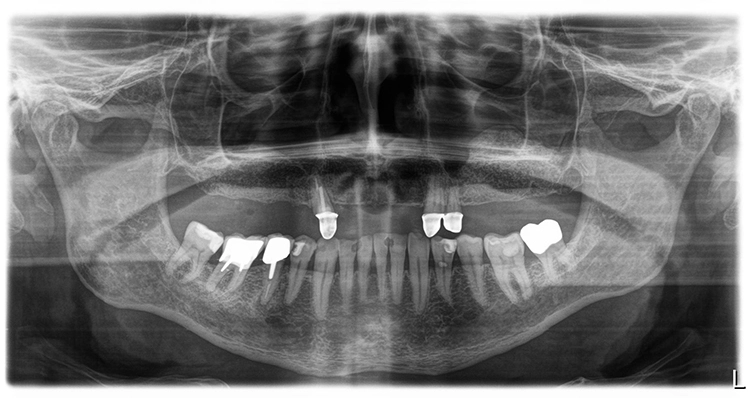

Der Patient ist Nichtraucher mit gutem Allgemeinzustand und nach Anamnese ohne kritische oder für einen eventuell notwendigen Knochenaufbau risikobehaftete Komorbiditäten [3]. Seine Teleskopprothese im Oberkiefer war nur noch über die drei Pfeilerzähne 13, 22 und 23 verankert.

Der Therapieplan wurde in Abstimmung mit dem Patienten erstellt. Dabei war zu berücksichtigen, dass der Patient über den gesamten Behandlungszeitraum bis zur Fertigstellung der definitiven Restauration unbedingt kaufunktionell versorgt zu bleiben wünschte, da er zwischenzeitlich in Campingurlaub gehen wollte. Aufgrund der starken Pneumatisation der Kieferhöhlen wurden im posterioren Bereich beidseitig ein externer Sinuslift und nach Ausheilung der Strukturen die Implantation von sieben Implantaten (Conelog, Camlog, Wimsheim) mit unterschiedlichem Durchmesser und je 13 mm Länge geplant.

Die Implantatmaße und -positionen sowie der Umfang der Sinusbodenelevation wurden dabei in Sinne eines „backward planning“ anhand von DVT-Aufnahmen bestimmt. Zahn 13 sollte noch vorübergehend erhalten bleiben, um zusammen mit den bleibenden Zähnen 23 und dem entsprechend kariesbehandelten Zahn 24 bis zur Fertigstellung der definitiven Restauration der alten Teleskopprothese als Interimsersatz Halt zu geben. Als definitive Versorgung wurden drei VMK-Brücken auf NEM-Gerüsten vorgesehen. Damit sollte auch die natürliche Bezahnung im Unterkiefer von 37 bis 47 abgestützt werden.